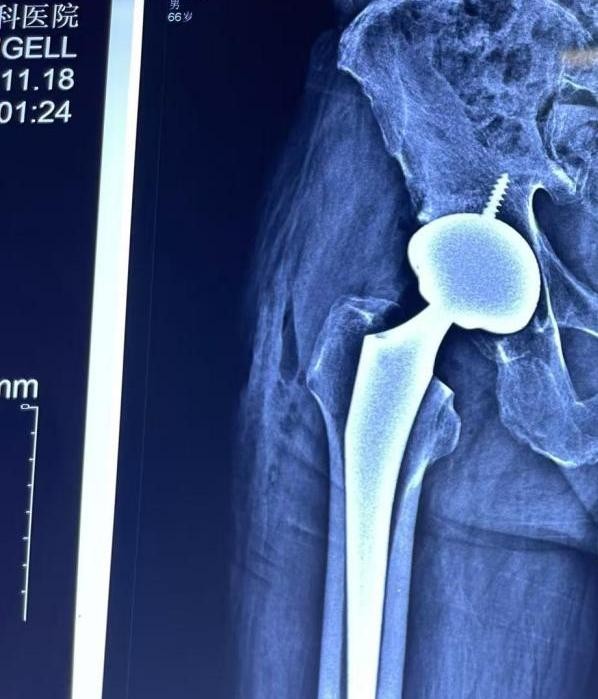

住院后,关节外科医生对患者进行了详细的术前评估,目前患者血压、血糖控制平稳,无手术禁忌症,考虑到他年龄才66岁,所以建议选择目前来说最耐磨的全陶瓷界面假体,不出意外的话可以使用30年以上,这样基本一次手术就可以解决困扰他多年的问题,在详细听取了各种假体的优缺点后,刘大哥欣然接受了医生的建议,手术于10月27日顺利进行。手术进程顺利,术中出血量仅约 100 毫升,术中人工关节安置准确,各个方向活动关节无脱位倾向,双下肢长度等长,平安返回病房。